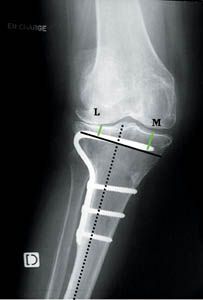

Technique Prothèse totale de genou et ostéotomie tibiale associée , Claude Vielpeau CHU de la Côte de Nacre, 14033 Caen, France , B. Level CHU de la Côte de Nacre - 14033 Caen Cedex , M. Michaud CHU de la Côte de Nacre - 14033 Caen Cedex N°128 - Novembre 2003 ● 11 min de lecture